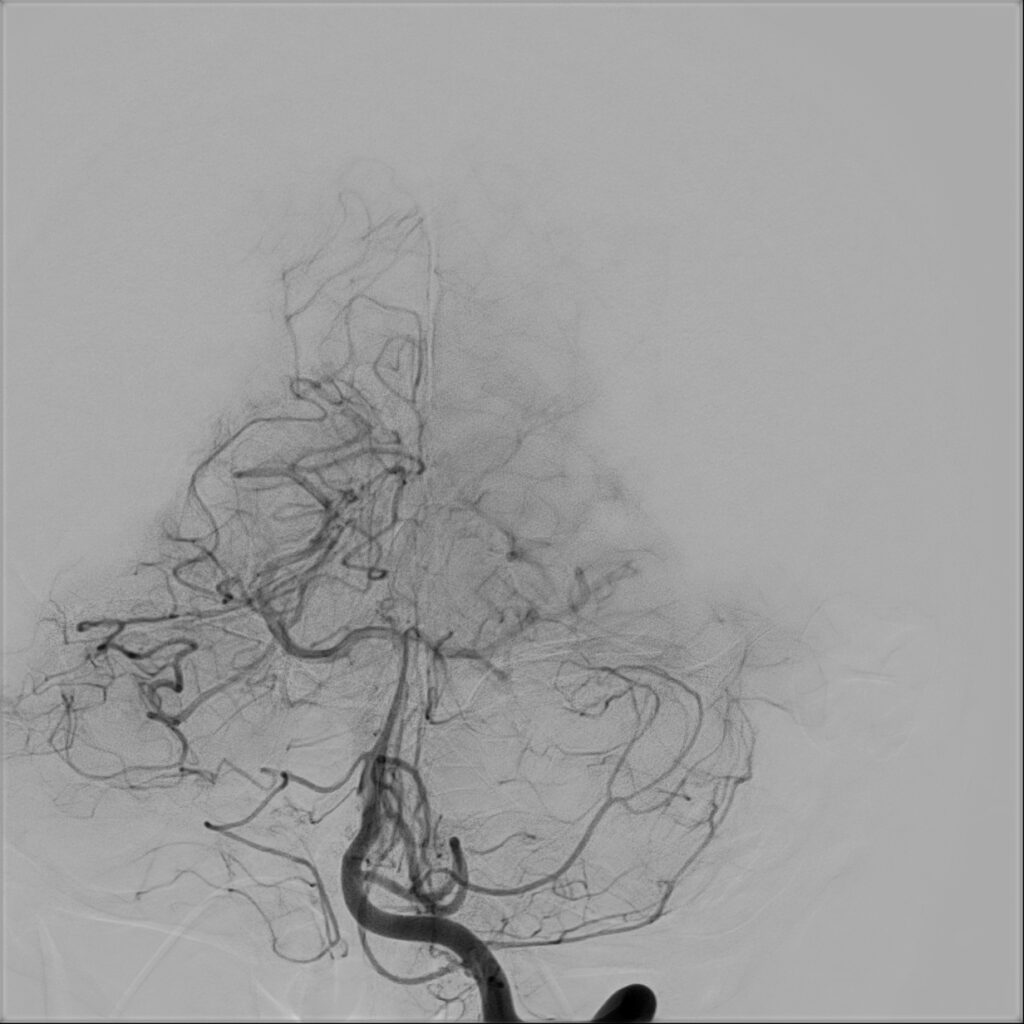

W badaniu tomografii komputerowej (TK) głowy oraz angio-TK stwierdzono krwawiącą malformację tętniczo-żylną (AVM) zlokalizowaną w lewej półkuli móżdżku.

W przypadku prezentowanej pacjentki nie stwierdzono objawów neurologicznych poza bólem głowy. Po wstępnej diagnostyce została przekazana do Oddziału Neurochirurgicznego Szpitala Kopernika w Łodzi. W trybie pilnym wykonano angiografię cyfrową (DSA), która precyzyjnie uwidoczniła AVM.

Przeprowadzono embolizację części tętnic zaopatrujących AVM, co zmniejszyło ryzyko krwawienia śródoperacyjnego. Następnie wykonano kraniotomię podpotyliczną lewostronną z całkowitym usunięciem malformacji. Zabieg przebiegł bez powikłań, po zabiegu u pacjentki nie stwierdzono deficytów neurologicznych. Kontrolna angiografia potwierdziła całkowite usunięcie zmiany, co pozwala uznać pacjentkę za wyleczoną.